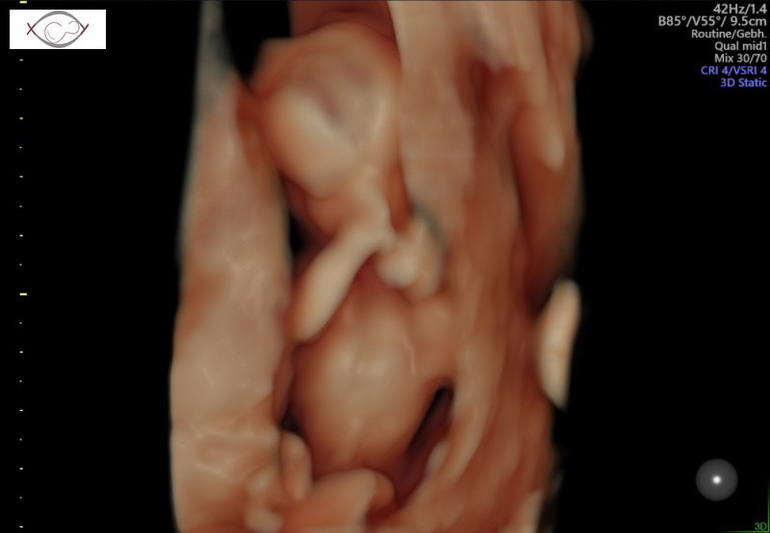

Посещение и назначения врачей (стоматологи, кардиологи и проч.)Сегодня ездила на первый скрининг. Естественно волновалась всё время пока ждала. Ожидание мне вообще не легко даётся, хочу всё и сразу🤪Как в фильме Человек с бульвара Капуцинов: "Джонни, сделай мне монтаж" 🤣🤣🤣 А ещё почему то больше пугает когда прям всё черезчур хорошо. Надо тут же выискивать что то, переживать, как то не укладывается в голове что всё хорошо🤷♀️Ещё 2 недели назад мой гинеколог развёл руками над моими анализами и произнёс" мне особо нечего Вам сказать, у Вас идеальная беременность" 🤷♀️ И вот сегодня в пренатальном центре - развитие день в день, кровоток отличный, всё как по книжке. Риски трисомии, конечно, есть, всё таки возраст, но это стандарт, совсем без рисков не бывает. Но нипт на всякий який, конечно, сдала🤪 Плюс уже пол хоцца узнать, лопну от любопытства. На УЗИ кроха стеснялся и прятался, разбудили его 😅. А меня всё дальше начинает тревожить, что слишком хорошо всё, так не бывает😬😬😬 С другой стороны, только второй триместр начался, цвяточки ещё впереди😬